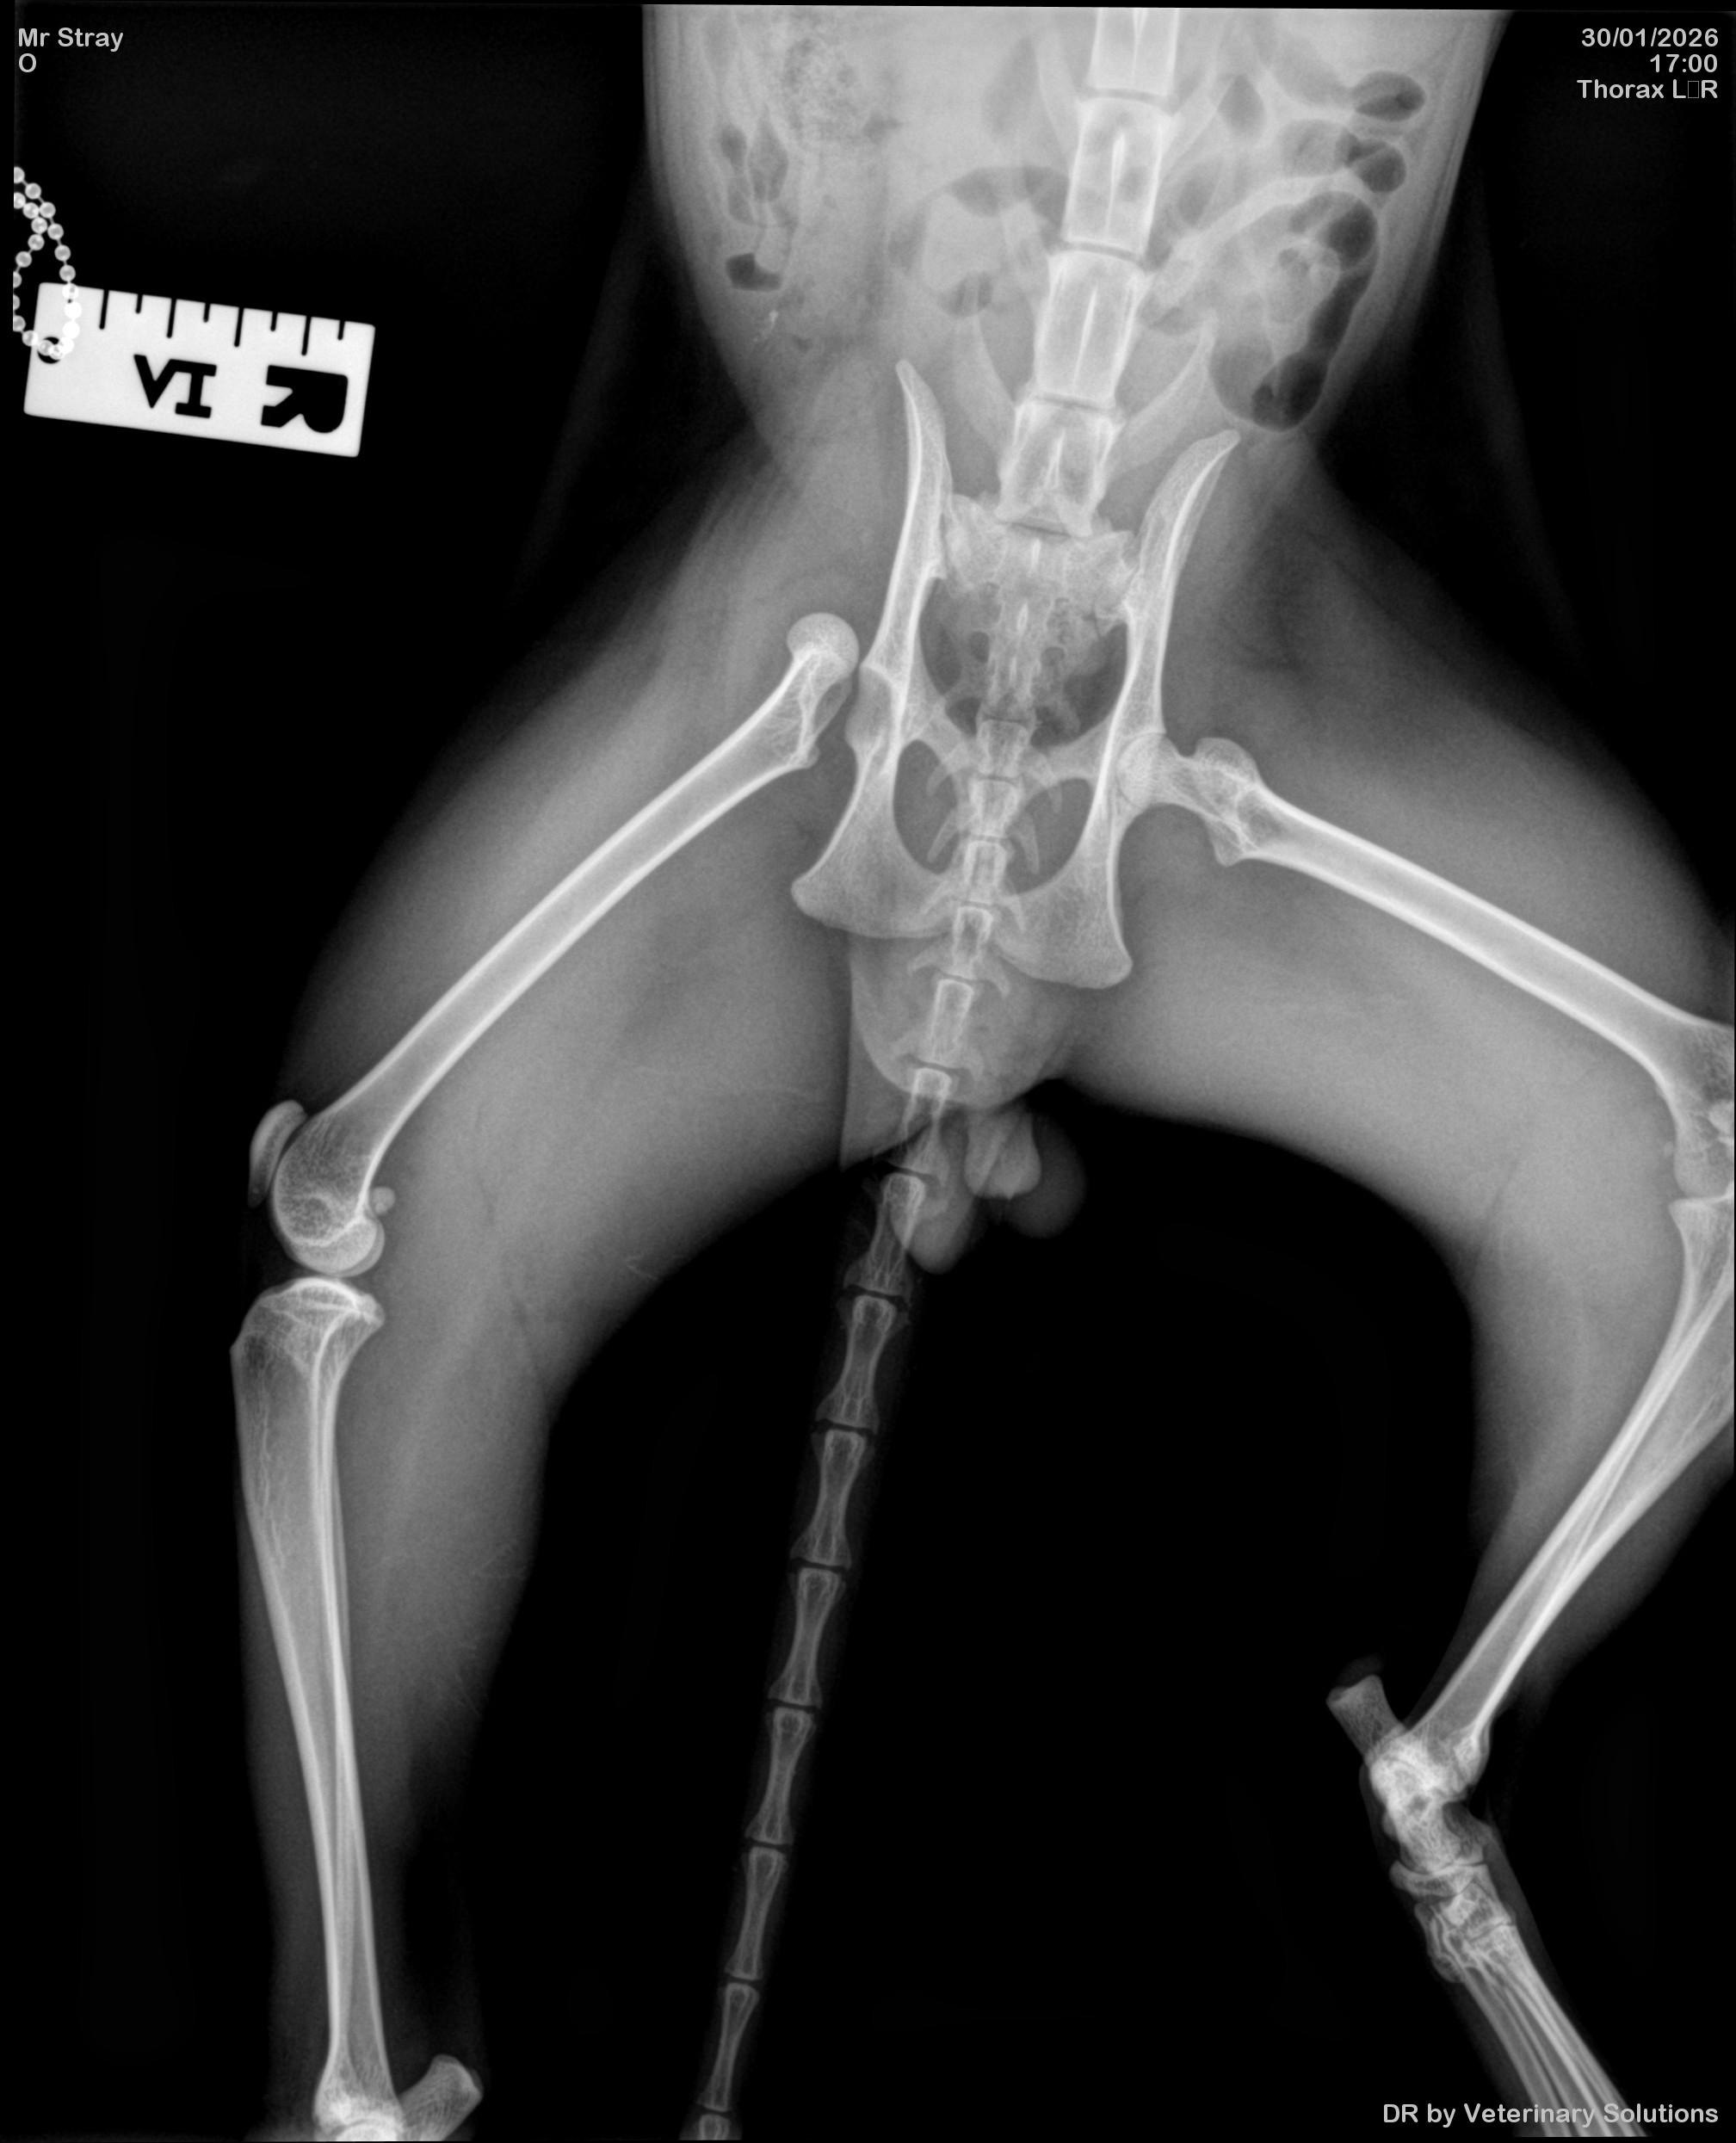

Elvis is a 3-year-old stray boy coming into our care after being hit by a car and left with a badly dislocated femur. He’s in pain, frightened, and had no one to speak for him - no owner, no safety net, no plan for treatment. That changed the moment he was found. Now, he has us - and we’re hoping, he’ll have you too.

We were faced with a heart-breaking decision: amputate or attempt complex surgery to save Elvis’s leg.

Choosing to save his leg means advanced orthopaedic surgery and a carefully managed recovery. It also means a vet bill currently estimated at over £3,000. We believe he deserves the option that gives him the best long-term comfort, mobility, and dignity - not simply the cheapest solution.